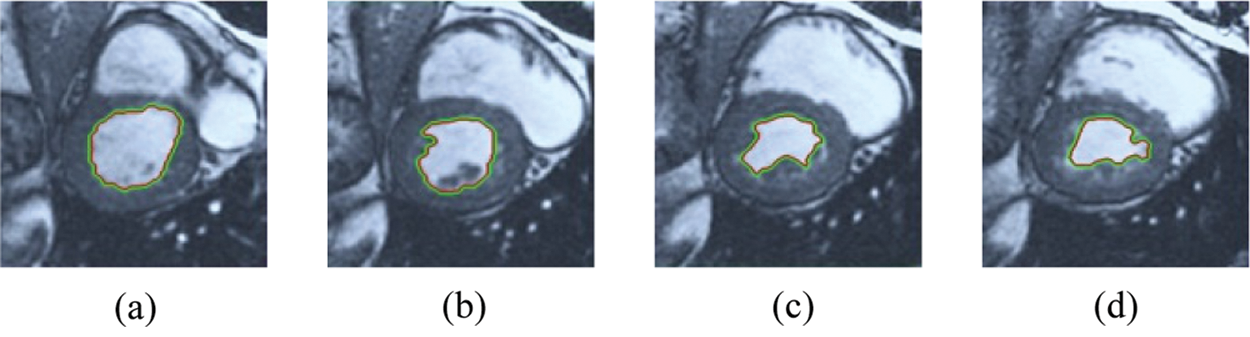

The BRW, HSRW, and ERW medical imaging segmentation schemes are executed on MATLAB, and examined on a short-axis of 3D multi-slices CMRI dataset [27]. Several segmentation performance metrics are utilized such as Dice Metric (DM), the Haussdorff distance (HS), and the Peak signal to noise ratio (PSNR). The BRW, HSRW, and ERW segmentation schemes are executed on a short-axis of 3D multi-slices CMRI datasets. The same multilayer CMRI dataset is segmented using various random walk methods. The presented results were obtained through using BRW, HSRW and ERW methods on five different groups of patients; each group contains 25 subject of multilayer CMR dataset. Experimental results illustrate that the BRW method can achieve a good segmentation of the LV cavity. The results of the HSRW algorithm have very comparable similarities to BRW, but with a slightly less efficiency and a much higher execution rate. Pre-calculations reduce the performance online time in offline mode. The average time of HSRW equals to 0.09 seconds for each slide. Raising the rate of K will improve the comparison and makes the process of segmentation more precise, but also reduces the execution time. The ERW technique results illustrate that this method has the greatest efficiency of segmentation. Figs. 5 to 7 show the resulting images of the BRW segmentation method on five sets of sample data. HSRW with pre-calculation segmentation method is applied on the same sets of sample data and illustrated in Figs. 8 to 10. Figs. 11–13 show the high efficiency segmentation using the ERW method with an earlier model for the same sets of sample data. The results of the Random Walk segmentation overcame the potential restrictions of the prior art CMR methods. The performance of segmentation is fast compared to segmentation methods based on edge and region. BRW precedes into account the properties of regions and edges, as shown in Figs. 5–7. Looking at the image as a graph, the technique makes it possible to integrate pixel relations with neighboring pixels. As a result, segmentation produces good quality BRW technique sections when their qualitative accuracy is compared to the ground truth, and this is also evident from the Tab. 1 measurements in the diastolic and systolic phases in Tab. 2 as well as in the complete cardiac cycle noticed. Figs. 8–10 illustrate the HSRW results. There are no dissimilarities observed in furthermost cases of CMR slides in the figures, but the correspondence measurements of the DM, PSNR and HS coefficients present that the results of the HSRW technique are worse than those of the BRW method. This presents that HSRW is an effective estimation of the random walk influence as mentioned in Tab. 1 and throughout the cardiac cycle in Tab. 2. The values of PSNR and DM are lower, whereas HS is higher than the BRW method, but with slight dissimilarities between HSRW and BRW methods throughout the blood circulation. The impact of execution eigenvectors pre-calculations is perfect when the execution time is faster than the BRW method and, in fact, more efficient than other segmentation method for LV heart segmentation. With the identical dataset, the ERW method shows a significant enhancement in efficiency, as presented in Figs. 11–13. From the scores, we can see that the segmentation is smoother and cleaner. The ERW method considers boundaries and areas, such as BRW, using the relations between adjacent pixels in the image. It also considers the additional regional advantage by including the assumptions that affect the results of the segmentation. Mean segmentation quality measurements are computed from the segmented images using correspondence measurements for instance DM, HS, and PSNR and verified for each method in the diastolic and systolic stages as presented in Tab. 1. Based on results, it can be determined that methods of random walk are enhanced in diastolic diagnosis and that their outcomes in the systolic stage are also of good efficiency. The results of the random walk segmentation methods in the complete blood circulation are shown in Tab. 2. The cardiac cycle similarity amounts indicate that DM and PSNR capacities of ERW are improved than the corresponding capacities in the case of the HSRW and BRW approaches; however, the HS measurements are lower than the equivalent measurements, as illustrated in Tab. 2. This designates that the ERW technique is the furthermost accurate segmentation technique among all the approaches stated above. The ERW technique has the uppermost value of PSNR, and the HSRW method has the lowermost value that denotes the uppermost speed in segmentation process.

Figure 11: ERW results for the first samples set

Figure 12: ERW results for the second samples set

Figure 13: ERW results for the third samples set